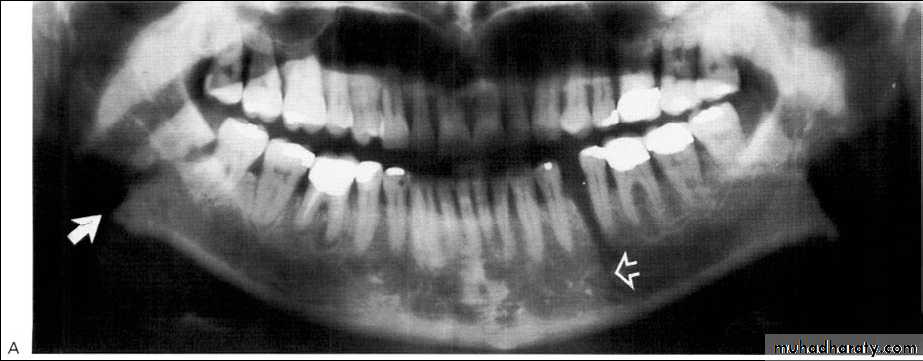

Central giant cell granuloma*A relatively uncommon, non- neoplastic mass in the jaws (intraosseous) producing an expansile radiolucent soap bubble appearance.

*Age; <20 years. Female > Male.

*Teeth are vital, with some root resorption & migration of teeth.

Multilocular appearance, expansion (arrowed) and considerable displacement of the adjacent teeth.

Buccal and lingual expansion (arrowed) and the undulating cortical border.

• Aneurysmal Bone Cyst

Large multilocular aneurysmal bone cyst

in the ramus with marked expansion andthe displacement of/8.

It is non-neoplastic ,exaggerated , localized, proliferative lesion of vascular tissue, containing giant cells.

It’s a variation of the central giant cell granuloma , can be diagnosed only by histological examination